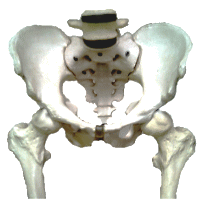

椎間板(軟骨)は、柔軟性に富んだ組織です。二本脚の生活で、背骨に重力が掛かると、椎間板は、徐々に薄くなって(潰れて)いきます。(中央上の画像)

夜、寝る状態になると、椎間板は、重力から開放され、周りの組織液を吸収し、元の厚みに戻ります。(右上の画像) 日々、それを繰り返しているのです。朝よりも、夜の身長が低くなるのは、この現象が原因の一つです。

つまり、椎間板(軟骨)が潰れているのは、寝ている間に、元の厚みに戻っていない状態です。戻らない原因は、寝る環境の問題や、個人の回復力の低下等があります。

仙骨がフリーズすると、椎間板に偏った圧力が加わるようになり、椎間板回復の妨げになります。